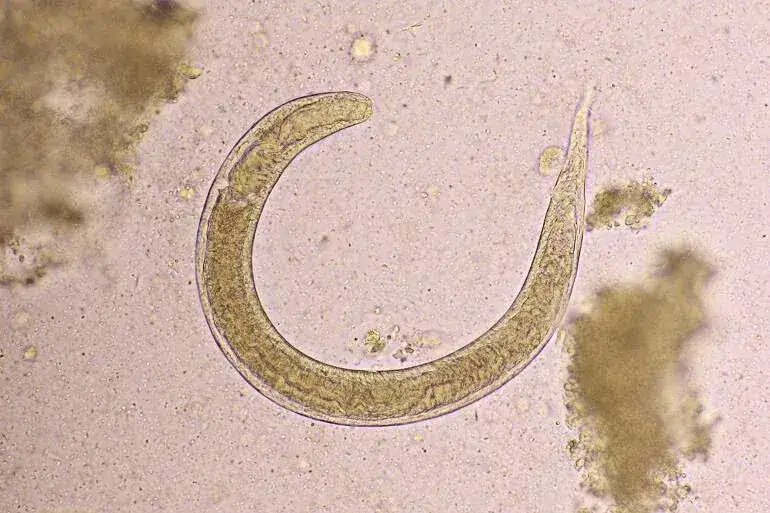

Czy leki na owsiki są na receptę? To pytanie zadaje sobie wiele osób borykających się z problemem owsicy. Owsiki to małe pasożyty, które mogą powodować dyskomfort i uciążliwe objawy, zwłaszcza u dzieci. Na szczęście, dostępne są różne leki, zarówno na receptę, jak i bez recepty, które mogą pomóc w ich zwalczaniu.